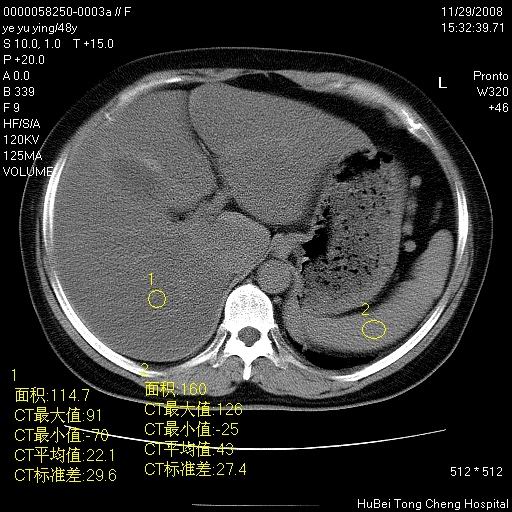

以下是引用zsl6918在2008-11-29 21:47:00的发言:[br]恶性肿瘤病史,转移瘤首先考虑。脂肪肝,胆囊结石。

以下是引用huenhao在2008-11-29 22:11:00的发言:[br]脂肪肝,胆囊结石。左肺病灶建议定期复查。

以下是引用liuyue在2008-11-30 5:44:00的发言:[br]1.左肺病变,首先考虑感染性病变,转移待排;建议治疗后复查。[br]2.肝脏密度普遍减低,考虑与化疗有关。[br]3.胆囊结石.